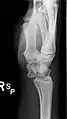

Dislocated lunate